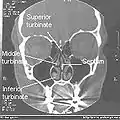

Illustration of upper respiratory system